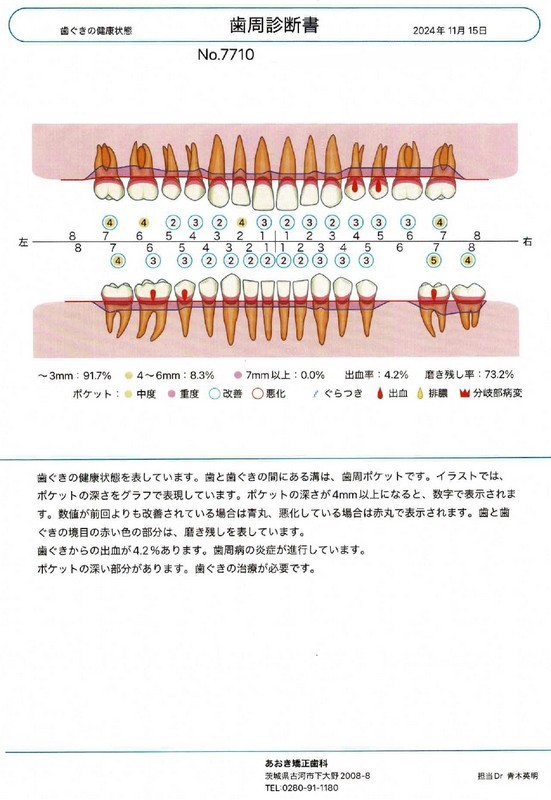

3週間後の再評価では、歯肉の発赤が明らかに改善し、腫れも引いてポケット深さは2~3 mmに改善。歯磨き時にも出血しなくなりました。

歯周病治療後

3週間後の再評価では、歯肉の発赤が明らかに改善し、腫れも引いてポケット深さは2~3 mmに改善。歯磨き時にも出血しなくなりました。

定期メインテナンス

現在はメインテナンス期へ移行し、約4ヶ月に1回の歯科衛生士による定期メインテナンスを継続。

定期メインテナンスの際には精密な歯周ポケット検査を実施し、安定した口腔環境を維持しています。